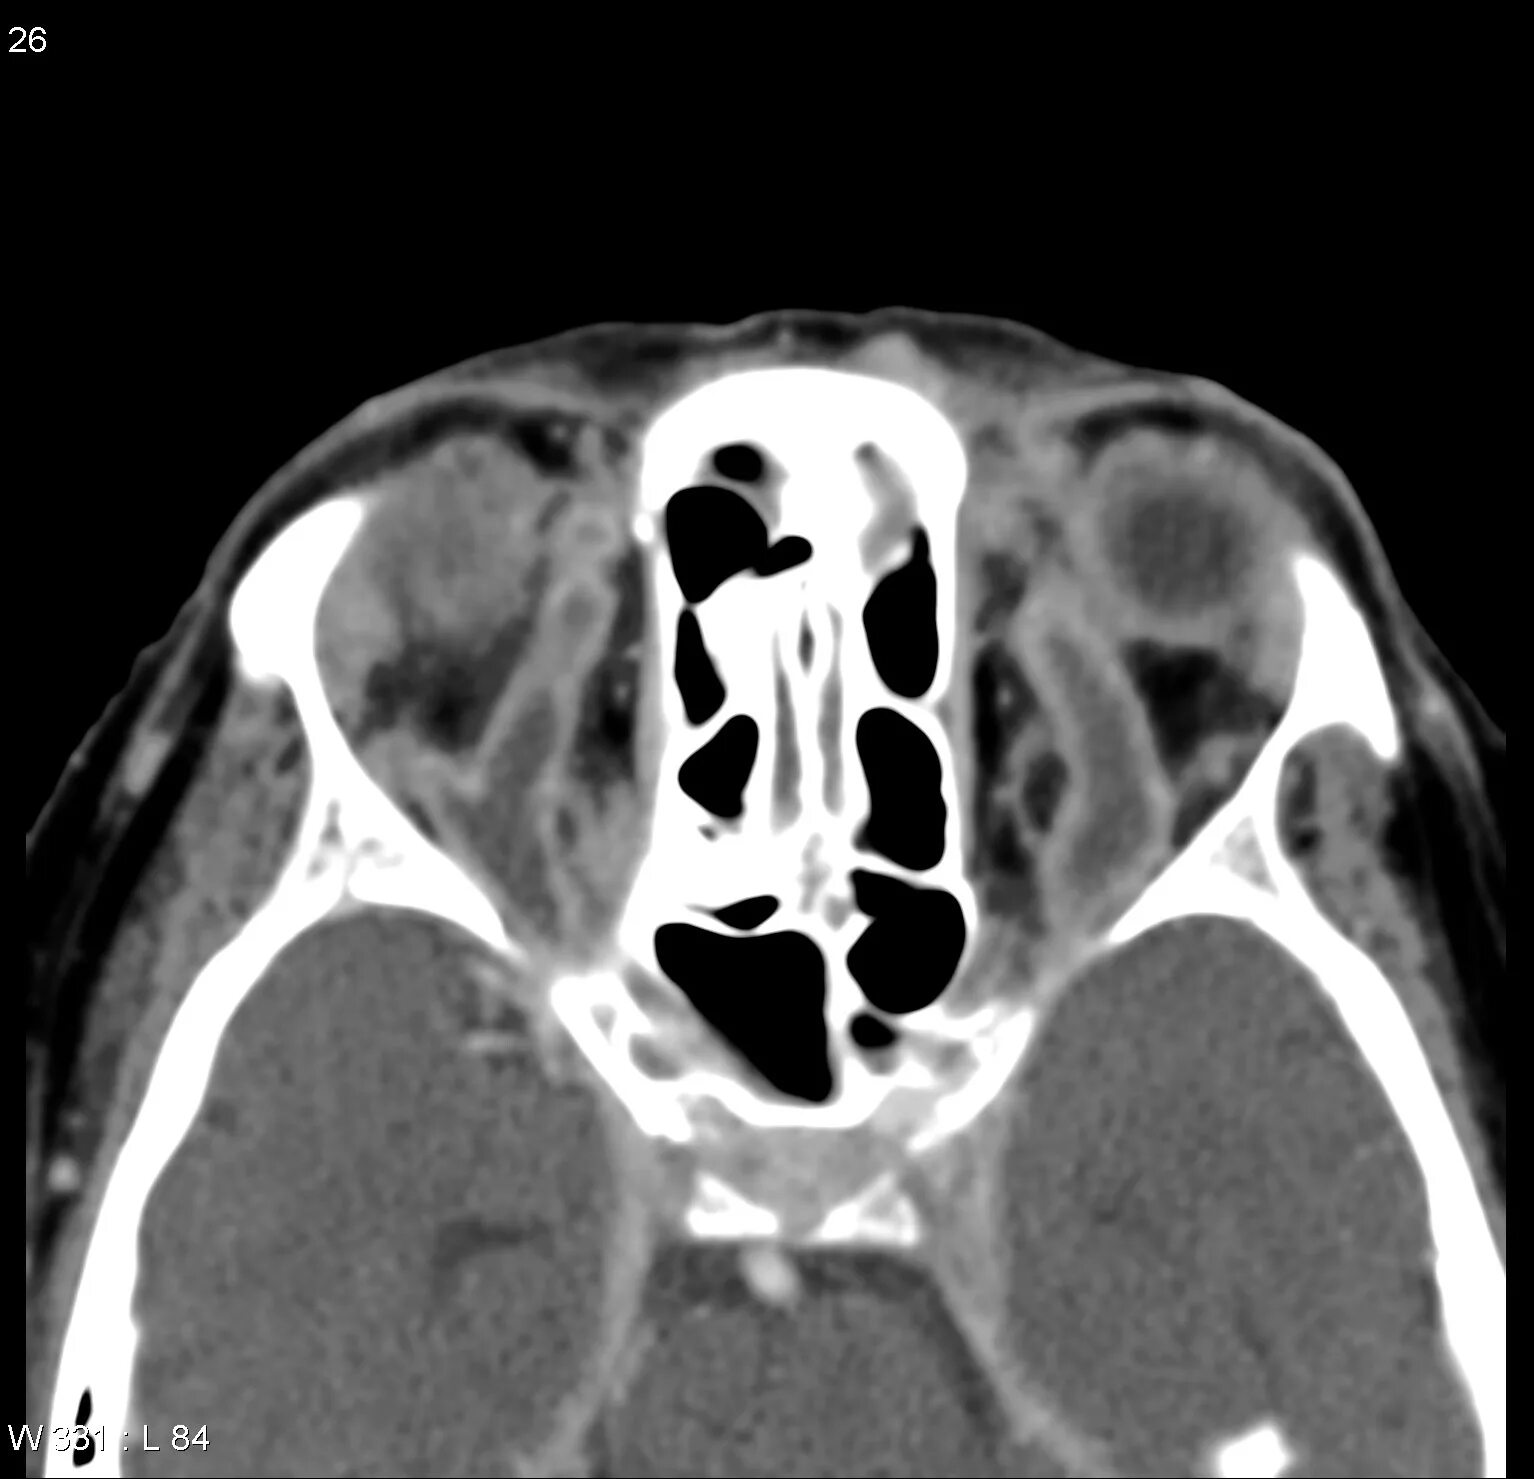

Тромбоз кавернозных